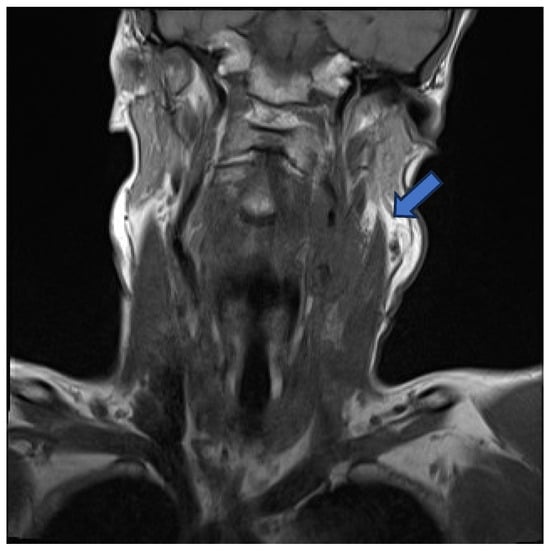

Initial contrast-enhanced computed tomography (CT) neck revealed a large left-sided neck mass, measuring 3.5 by 4.6 cm. Further characterisation by contrast-enhanced magnetic resonance imaging (MRI) showed the neck mass to be encasing the upper common carotid artery, the carotid bulb, and the internal carotid artery on the left side. This mass was also compressing the left internal jugular vein, occluding it and resulting in thrombosis (Figure 1).

Figure 1. MRI—mass encasing the left common carotid, carotid bulb, and internal carotid arteries (blue arrow).